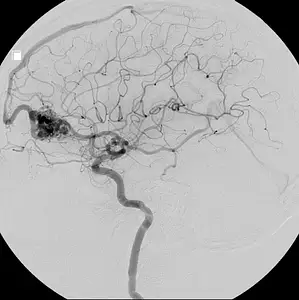

Arteriovenous Malformation (AVM)

Like all organs, our brain relies on arteries to bring oxygenated blood from the heart and veins to return oxygen-depleted blood. In cases of an AVM, an abnormal tangles of vessels interrupt the flow of blood and deny areas of the brain the oxygen they require. Over time, these abnormal vessels may weaken and rupture, leading to hemorrhage, stroke, or brain damage.